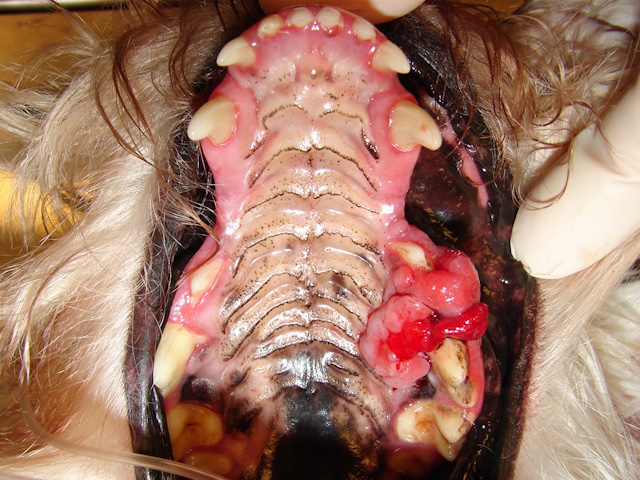

Severely inflamed gums and oral mucosa affecting the third and fourth premolar area. Deep biopsy of this region revealed squamous cell carcinoma.

Hyperplastic, ulcerative and bleeding lesion in the caudal mucosa and mandible. Biopsy showed squamous cell carcinoma.